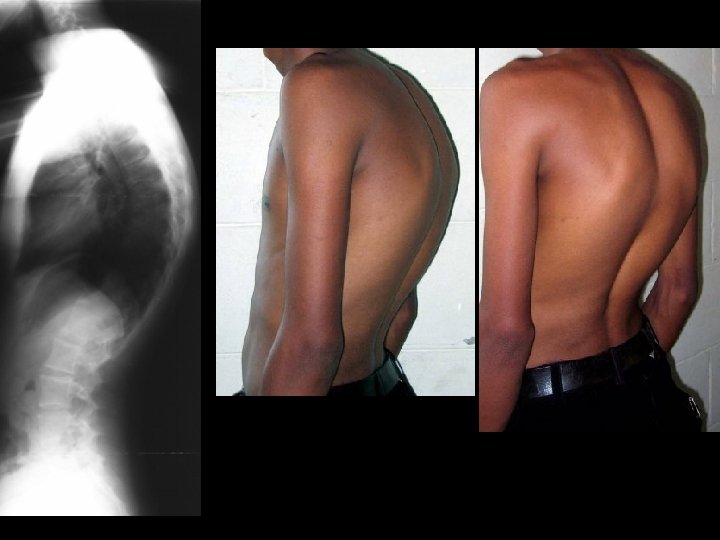

Neuromuscular Curves

Pelvic Obliquity

Non- Structural: Does correct on bending x-rays Standing Left Bend

Structural: Does NOT correct on bending x-rays Standing Right Bend